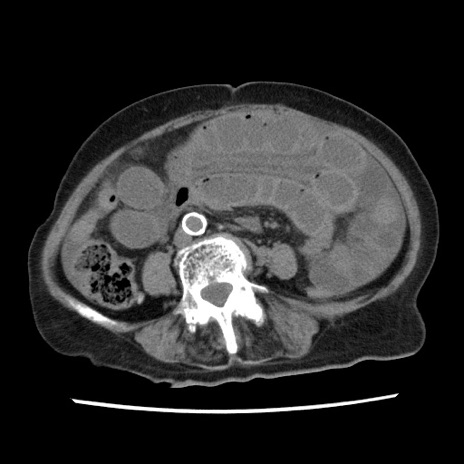

症例1(横断像)

【症例】80歳代女性

【主訴】腹痛

【現病歴】8時間前から腹痛あり来院。

【既往歴】糖尿病、脂質異常症、子宮体癌にて子宮全摘術

【身体所見】意識清明・会話良好だが腹痛で苦悶様、全腹部にわたって反跳痛と圧痛あり

【データ】WBC 13600、CRP 0.14、LDH 224、CK 90